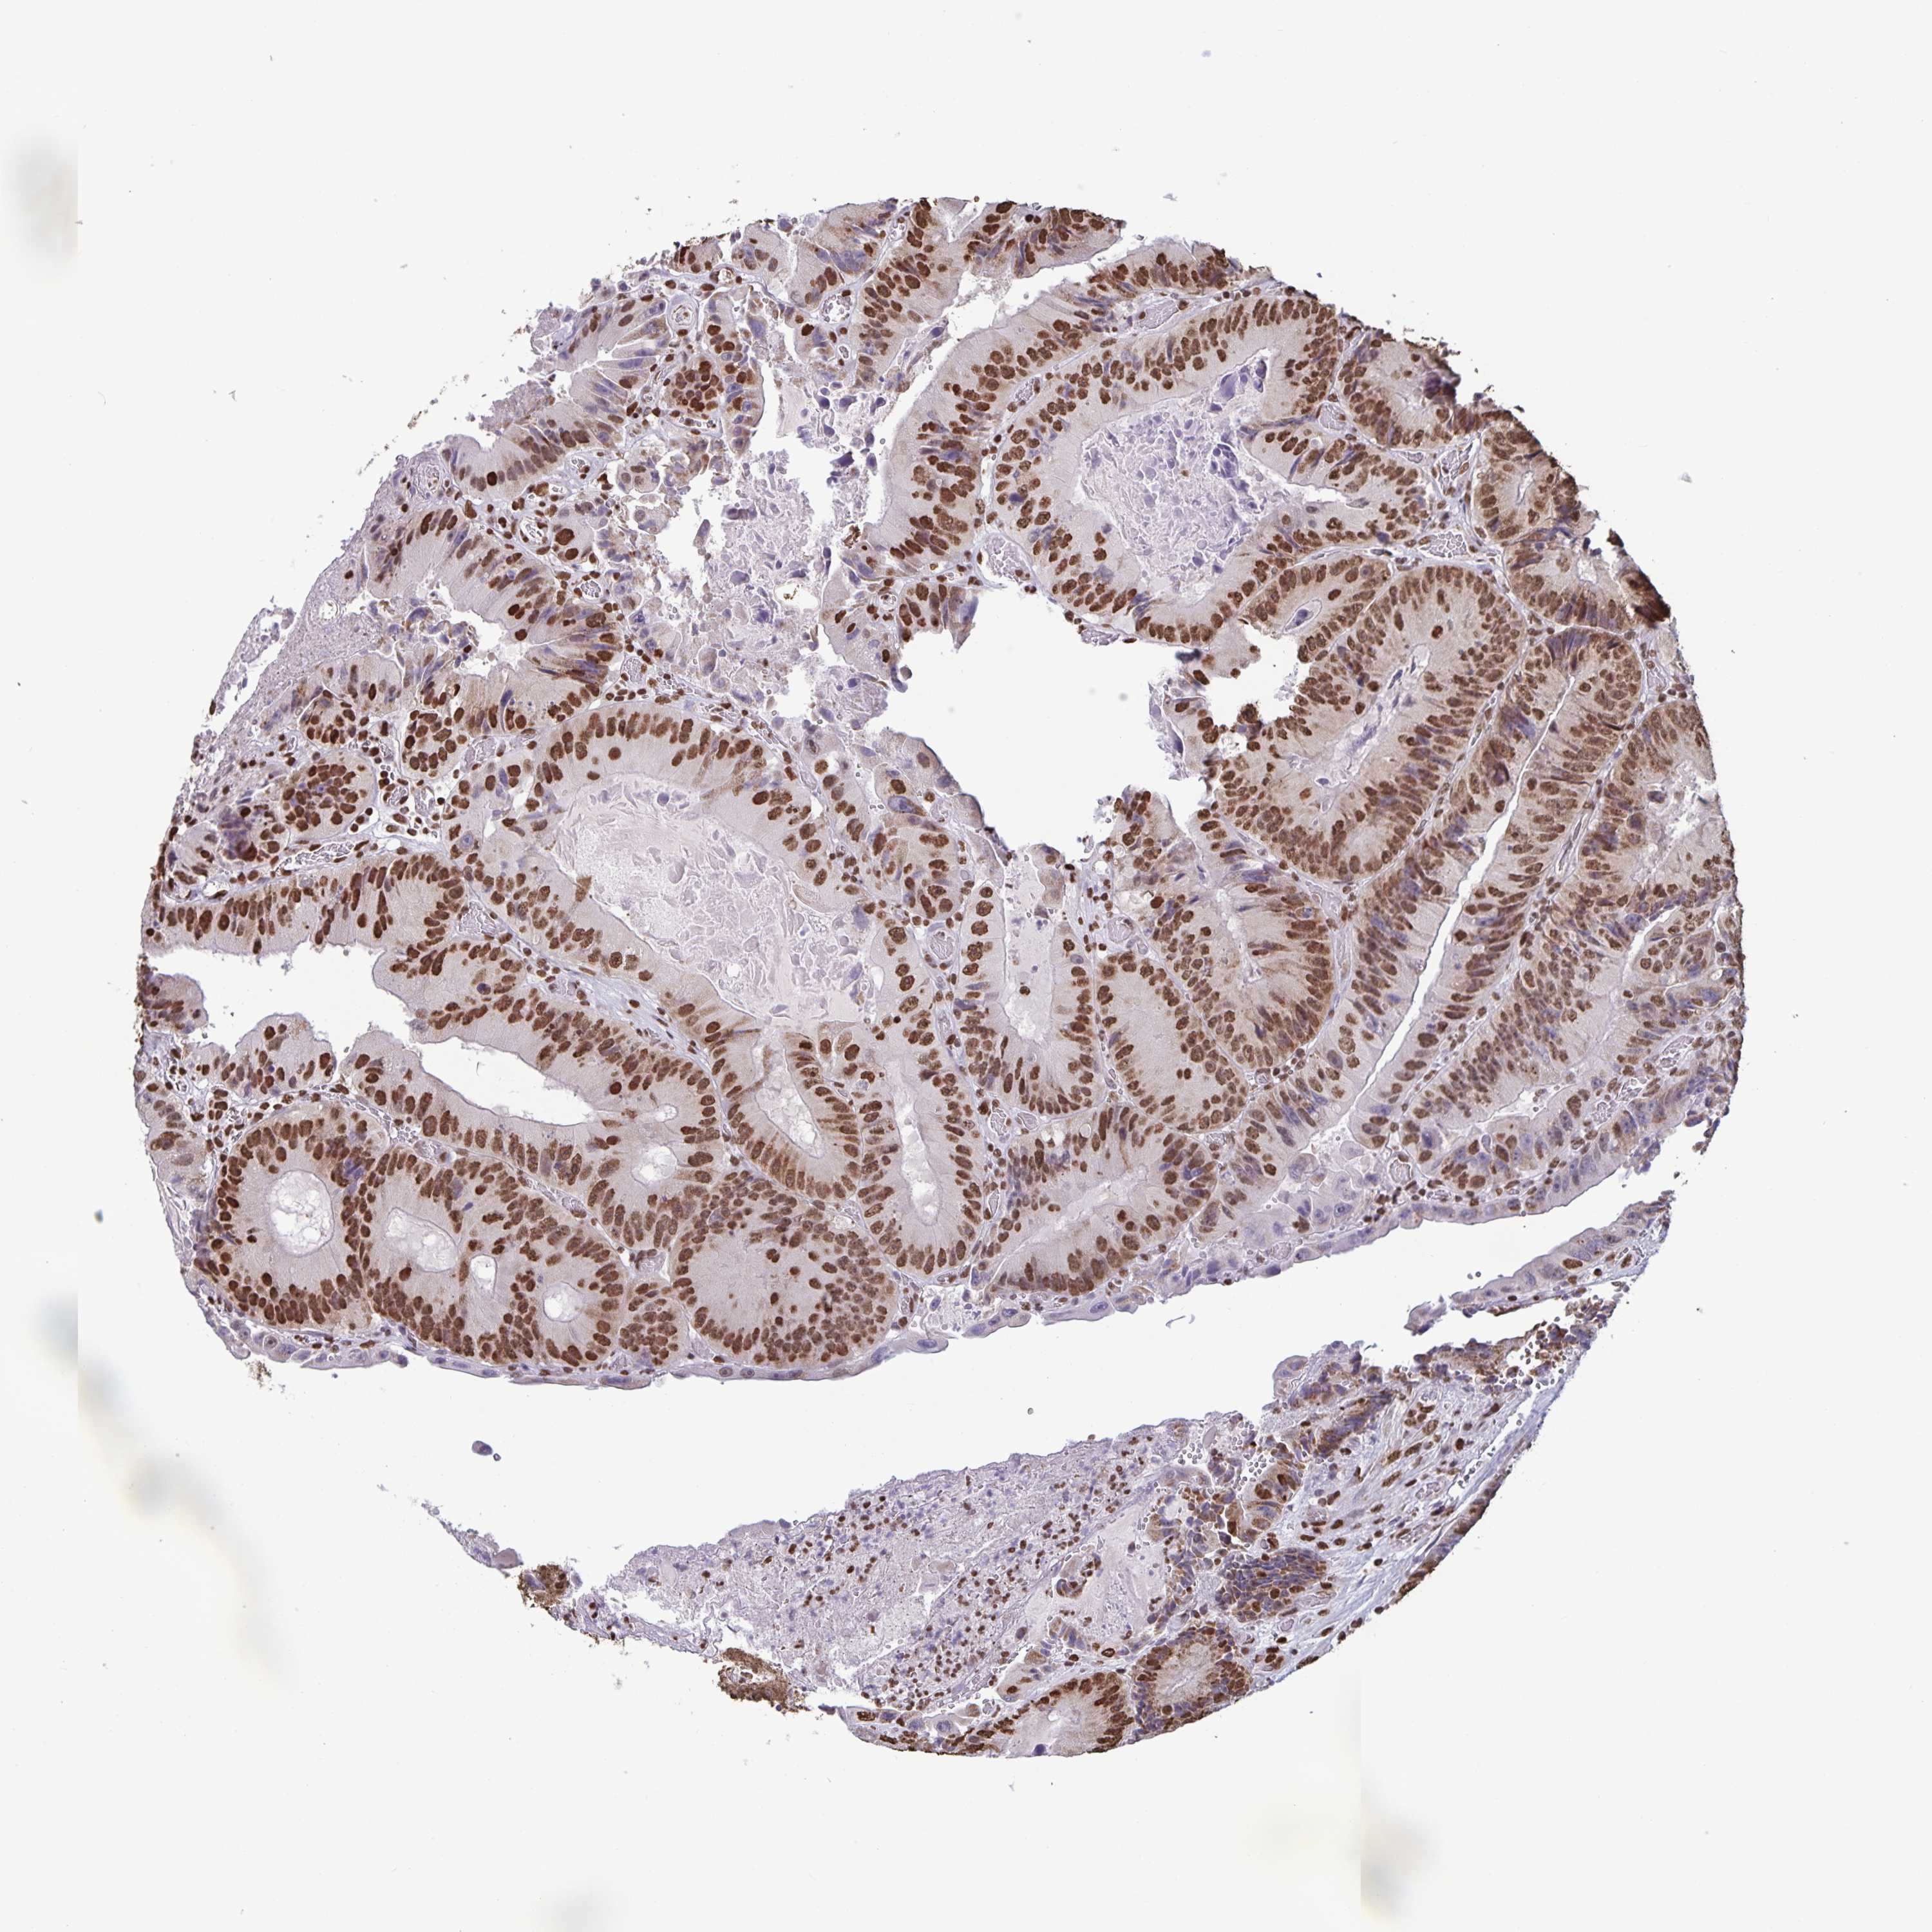

CANCER COLORECTAL CANCER Show tissue menu

Colorectal cancer

Human cancer

Colon adenocarcinoma